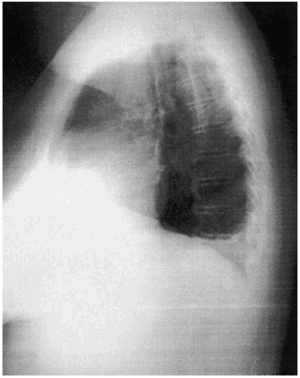

Mujer de 49 años con antecedentes personales de HTA y enfermedad pélvica inflamatoria sin secuelas. Ingresa por dolor abdominal, nicturia y edemas en miembros inferiores de 2 meses de evolución. En la ecografía realizada se apreció una masa abdominal de gran tamaño compatible con mioma uterino. Se intervino de forma programada con histerectomía total ampliada. Dos días después desarrolló hipotensión arterial, oliguria y marcado aumento de los edemas, por lo que finalmente fue preciso su ingreso en UCI. Destacaban signos de bajo voltaje en el ECG, mínima cardiomegalia y ligero derrame pleural derecho en la radiografía de tórax (figs. 1 y 2). Se realizó ecocardiografía transesofágica de urgencia donde se objetivó una masa en la aurícula derecha de 3,7 ×7 cm, de consistencia heterogénea, con punto de implantación en zona inferior del septo interauricular, que invadía el ventrículo derecho y ocupaba la mayor parte del anillo valvular auriculoventricular (fig. 3). La interpretación ecocardiográfica fue de trombo intracardíaco o mixoma auricular derecho. La paciente se intervino quirúrgicamente y se confirmó este último diagnóstico.

Figura 1.